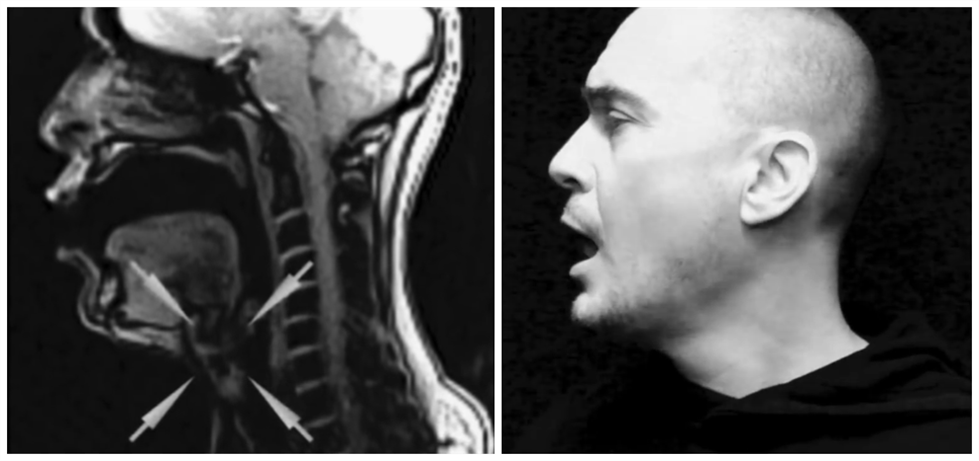

科学有意思 | 声音是如何从喉咙发出的?在核磁共振下唱歌试试

图片尺寸979x461